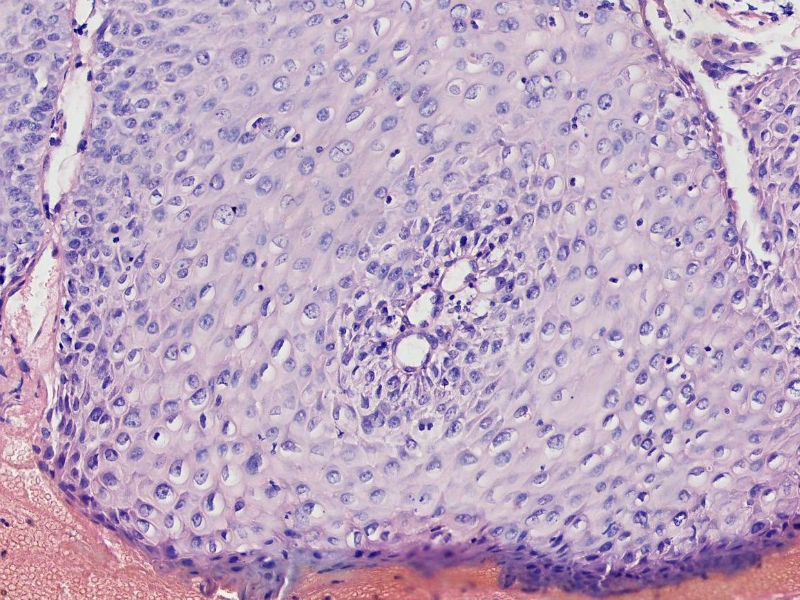

女45岁,宫颈口可见一突出物直径约0.5菜花状质脆

图1

细胞异型性不太大,考虑湿疣样增生

CIN3,伴湿疣感染

细胞异型不大,乳头状瘤。

乳头状的CIN,有平切,似乎有高级别的CIN,需除外癌。